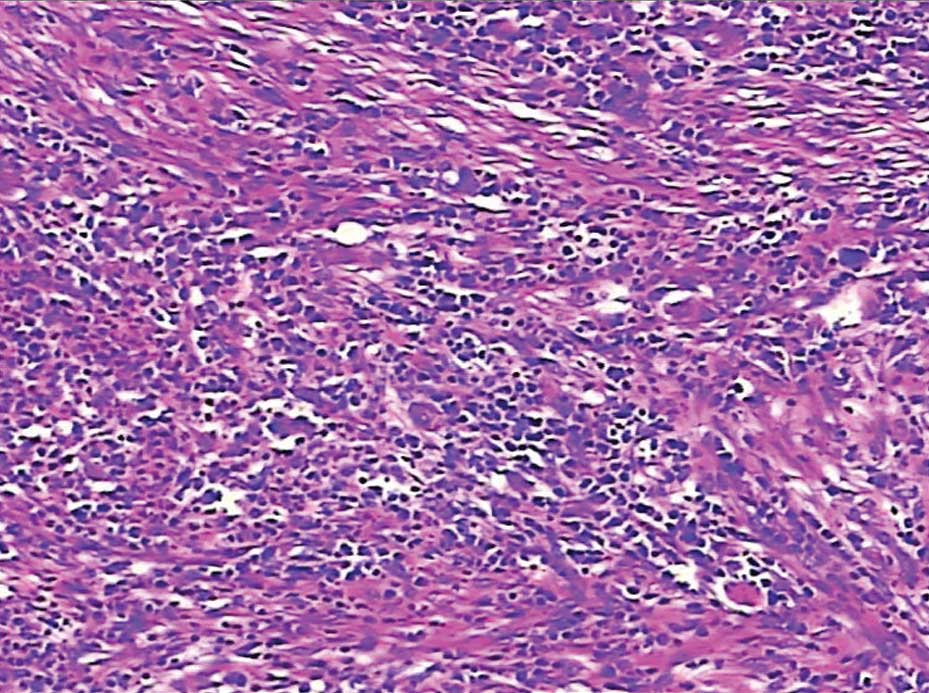

of retained local hemostat residue and pus (Fig. 4). Microscopic examination revealed a

fibrous encapsulation containing the foreign-body giant cell

reaction (Fig. 5). The surgeon who